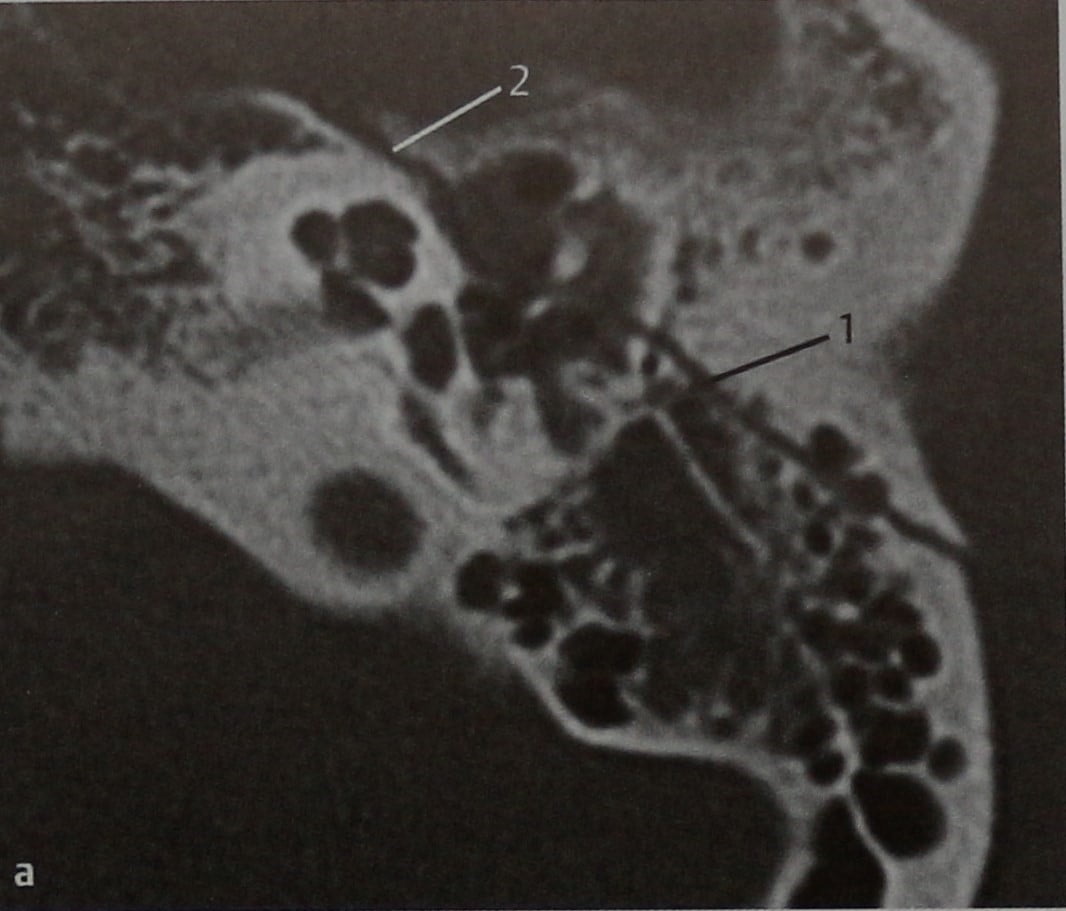

Анатомия сосцевидного отростка